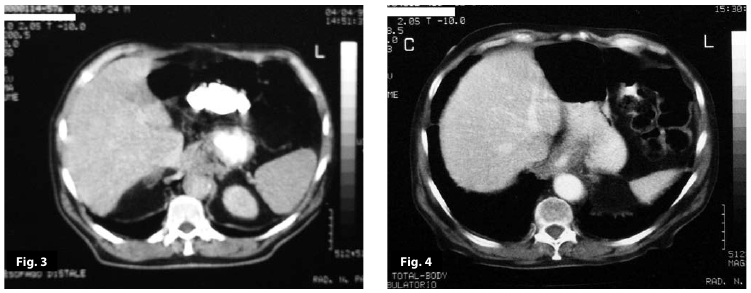

Figure3

Figure4

Figure3-4